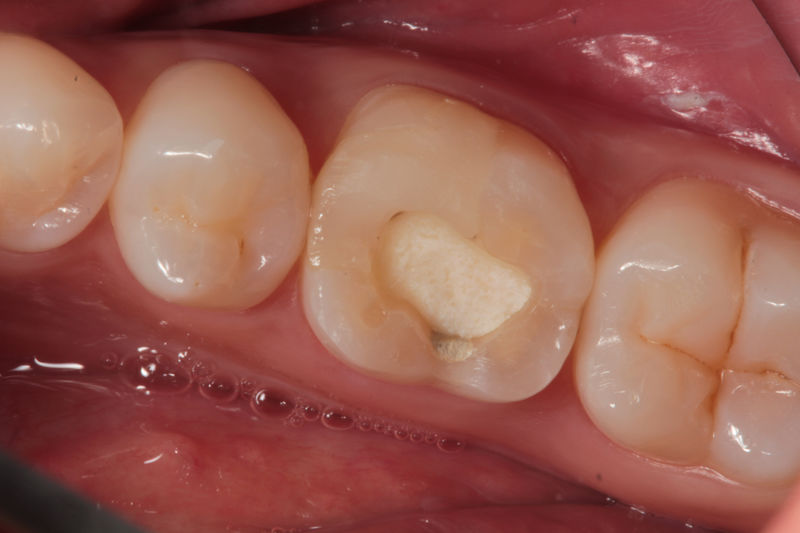

Son restauraciones con materiales plásticos color diente usados primariamente en dientes con caries pequeñas y puestas directamente en el diente.